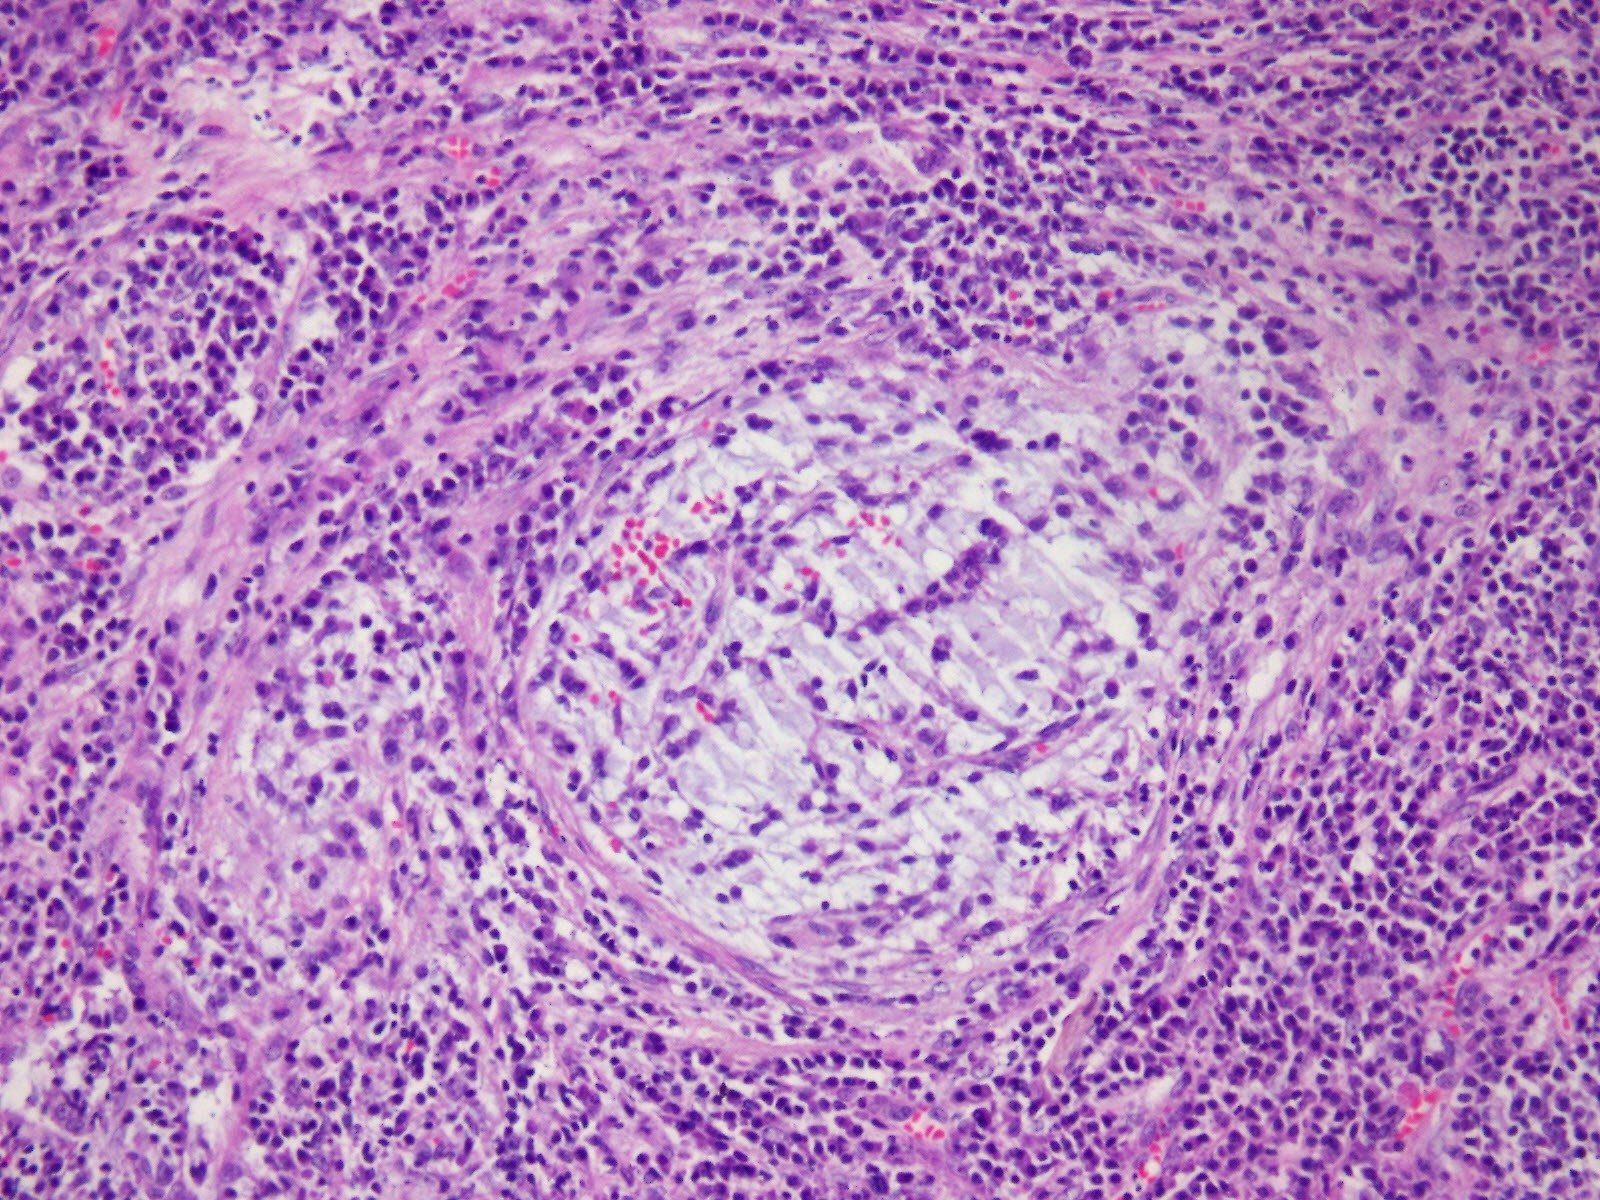

The tumor was a solitary, endobronchial, well-circumscribed mass with a fleshy uniform white and gelatinous cut surface that measured 2x1.7x1 cm. histologically, the tumour was multinodular, and its cells were small, ovoid or polygonal with vesicular nuclei resembling chondrocyte-like or physaliferous cells in a background of myxoid stroma (Figure 2). There were infrequent mitotic figures, as well as extensive lymphoplasmacytic cell infiltration (Figure 3).

Frozen sections revealed spindle cell proliferative lesions with a rich mucoid background and a significant lymphocyte and plasma cell infiltration. It was impossible to tell if it was benign or cancerous. The tumor cells were distributed in a nodular pattern with considerable collagen interstitium, according to H&E staining. Tumor cells were spherical and oval, organized reticularly or ribbon-like in a mucoid background (Figure 2,3). Tumor cell atypia was mild to moderate. Mitotic activity was less than 2/10 HPF (high-power fields). The tumor had a mucinous background, many lymphocytes and plasma cells in the infiltrate, and many spindle cells proliferated (Figure 4).